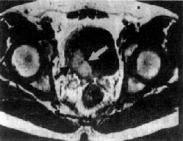

老年人膀胱癌